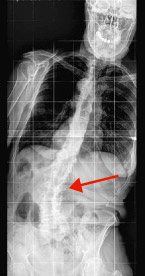

hirslanden-wirbelsaeuleneingriffe-beim-alternden-menschen-1

Abb. 1

Spinale Stenose (Wirbelkanaleinengung)

Spinale Stenose

Die Spinale Stenose ist eine Einengung des Wirbelkanals oder der Austrittsöffnungen des Wirbelkanals für die einzelnen Nervenwurzeln. Man nimmt an, dass die Einengungen eine Stauung des Blutes in den Nerven bewirkt und zu Schmerzen in den Beinen oder in der Lendenwirbelsäule führt. Die Patienten klagen dabei oft über eine deutliche Gehstreckenlimitierung: Nach einer kurzen Gehstrecke oder nach längerem Stehen müssen sie sich entweder hinsetzen, sich vornüberbeugen und abstützen oder in die Hocke gehen (Abb. 1).

Die Einengung des Wirbelkanals kann einhergehen mit einem so genannten degenerativen Wirbelgleiten, vor allem zwischen dem vierten und fünften oder dem dritten und vierten Lendenwirbel, ausgelöst durch eine Instabilität in einem Wirbelsegment durch Abnützung der kleinen Wirbelgelenke und der Bandscheibe. Zusätzlich wird die Stenose verstärkt durch die Verschiebung des Wirbels.

Bringen die konservativen (nicht-chirurgischen) Behandlungsmassnahmen nicht den gewünschten Erfolg, bleibt oft nur noch die Operation. Dabei wird der Wirbelkanal erweitert (Dekompression) und mit Schrauben und Stäben stabilisiert.